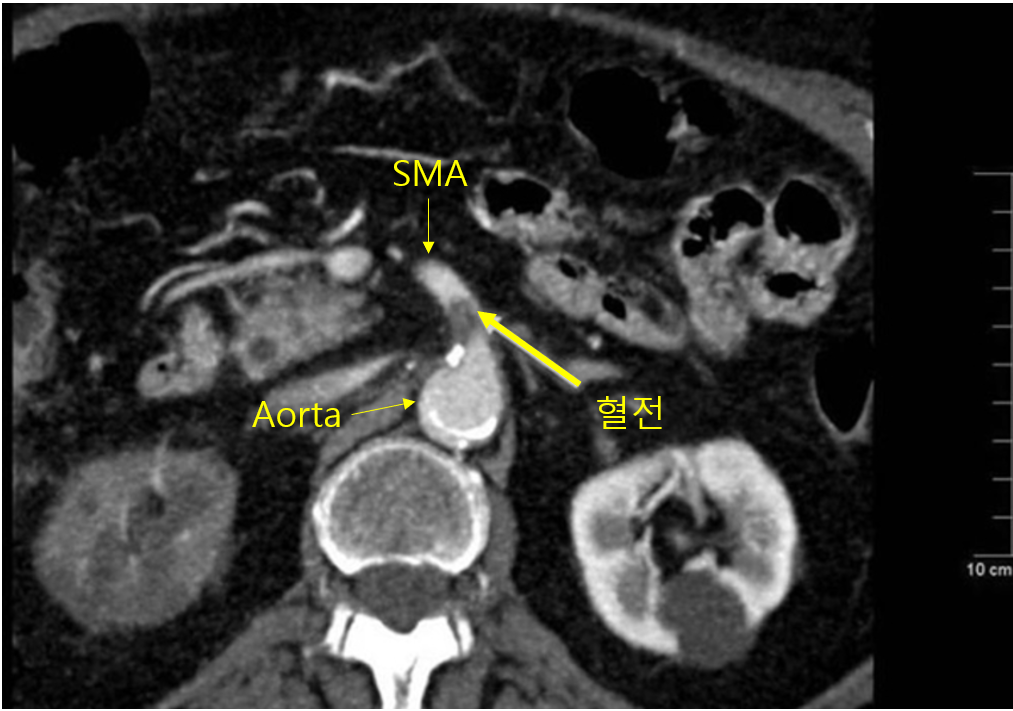

(2) 혈전이 동맥을 타고 가다가 superior/inferior mesenteric artery를 막음 (주로 SMA)

(1) 복부 CT(조영증강) + CT 혈관조영술

① 막힌 혈관의 위치 파악

② 괴사한 장의 유무 및 범위 파악